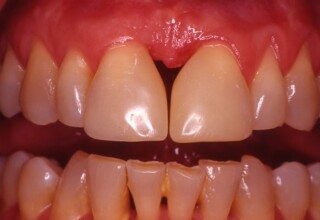

Restoration of bilateral diastemas between central and lateral incisors.

Diastemas were created mainly because of narrow laterals. After orthodontic treatment was finalized, the diastemas were closed with two composite resin restorations.